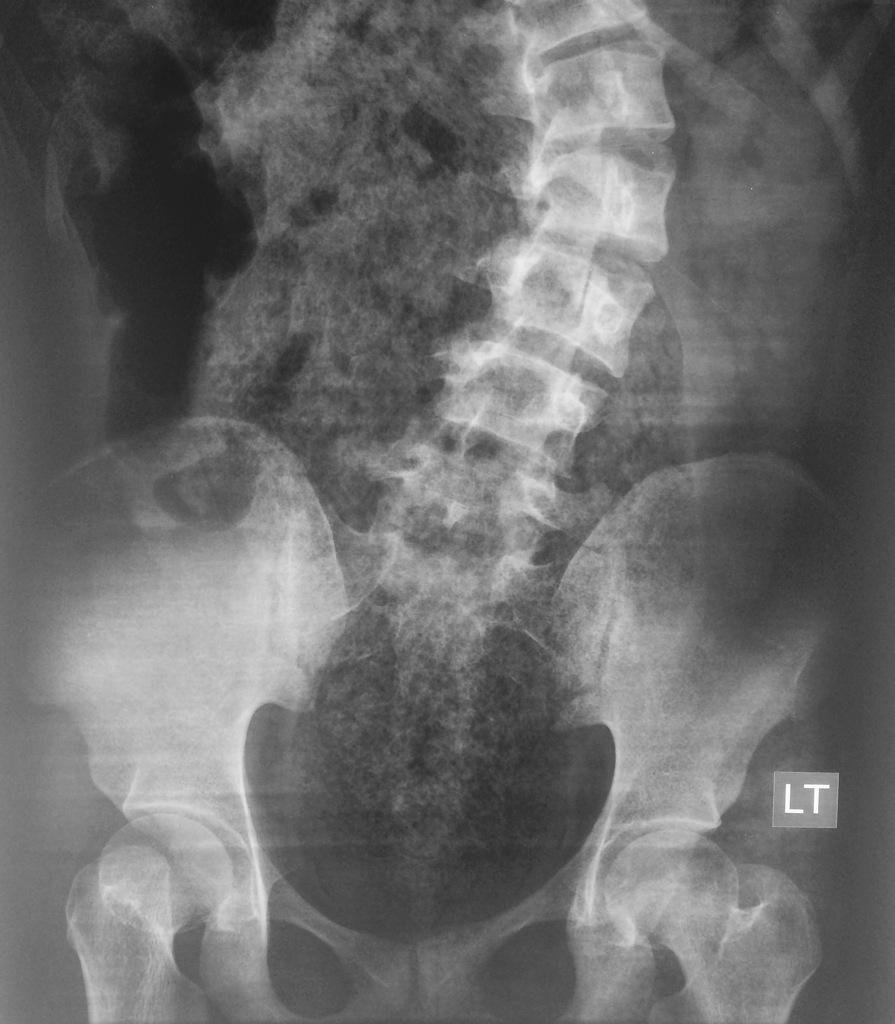

Constipation abdominal x ray wikidoc

Moderate stool burden with nonobstructive bowel gas pattern How To See Stool On X Ray Air under the diaphragms (intraperitoneal free air): These abnormal bowel gas patterns will appear the same whether imaged initially by conventional radiography or by ct scanning. Feces throughout the large bowel are well seen on abdominal radiographs, with a mixed radiographic density,. Gas/air is of low density and forms a natural contrast against. This can be suggestive of. One of. How To See Stool On X Ray.